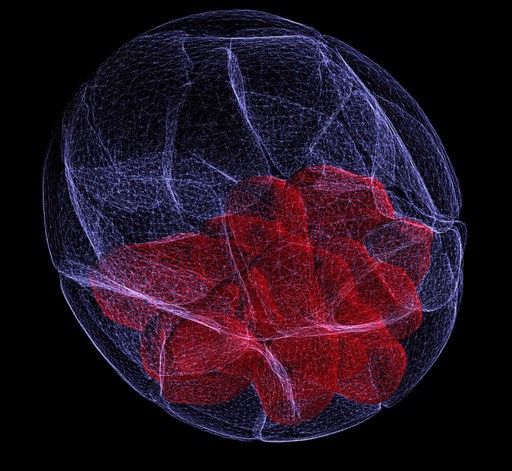

Two-photon microscopes

Two-photon microscopes use a scanning technique, fluorochromes and infrared light to visualize specimens. It is called two-photon because the low energy associated with longer wave lengths of light requires that two-photons must strike a location at the same time to excite the fluorochrome. Two-photon imaging is applied in intravital microscopy and deep tissue imaging due to the non-destructive low energy light used.

Although cost is a major barrier for two-photon systems, one area of biology that has benefited tremendously from the technique is immunology. Many important lymphocyte behaviors, such as antigen recognition, take place deep in densely populated lymphoid tissues. Knowledge about T cell development and B cell-T cell chemotaxis have been aided by this microscopy technique. Another area of research that has benefited from the incorporation of two-photon microscopy is infectious disease. The life cycle of malaria parasites involves infecting the liver. Two-photon imaging revealed parasites enter through Kupffer cells lining the liver sinuses, a fact unknown at that time. Tumor biology has also benefited from the incorporation of two-photon microscopy. Multiphoton intravital microscopy (IVM) has been used to monitor cell migration in tumors and metastasis. The IVM technique has revealed new roles for macrophages, the extracellular matrix, and stromal cells during tumor cell invasion. Beyond oncogenesis, IVM can been used to monitor responses to anti-angiogenic drugs which are used to destroy tumor vasculature. Surprisingly, results with IVM revealed these therapies may actually be working to normalize the tumor vasculature rather than destroy it.